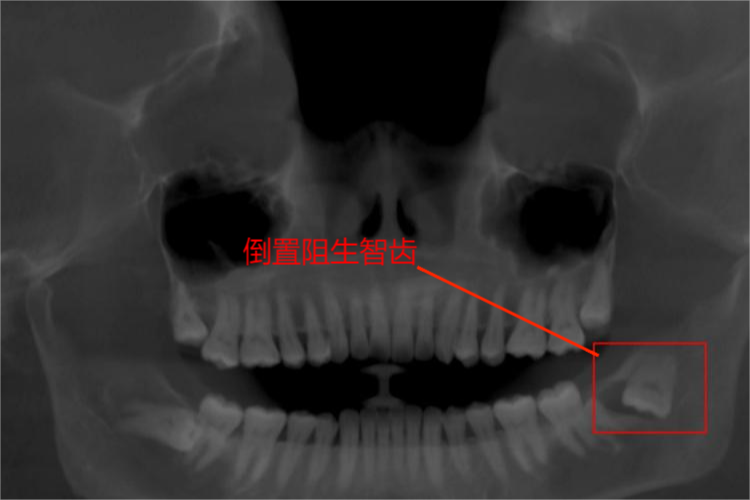

智齿倒着长为阻生智齿中的倒置阻生智齿,表现为牙冠与牙根倒位。

倒置阻生智齿表现为冠部向下,根部向上,与一般的牙齿位置完全相反,倒置于上、下颌骨内。另外,倒置阻生智齿患者常伴有智齿冠周炎,故可出现倒置阻生智齿周围的红肿、疼痛、张口受限等症状。随着病情加重,部分患者可出现发热、张口困难、局部剧痛、牙周红肿、局部冠周脓肿等严重症状。